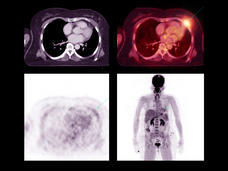

Dejar de fumar mejora la supervivencia de las personas con cáncer de pulmón

En un nuevo estudio, se observó que dejar de fumar después de un diagnóstico de cáncer de pulmón en estadio temprano ayuda a prolongar la vida de las personas. En el estudio, que incluyó a más de 500 pacientes, también se descubrió que dejar de fumar hace que el cáncer tarde más en recidivar (volver) o empeorar.